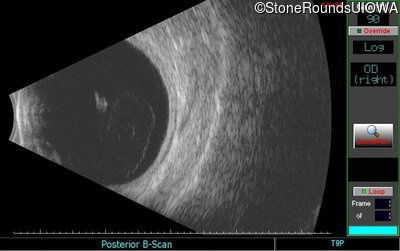

B-Scan Ultrasonography - Right - Count Fingers 2'

Exemplar